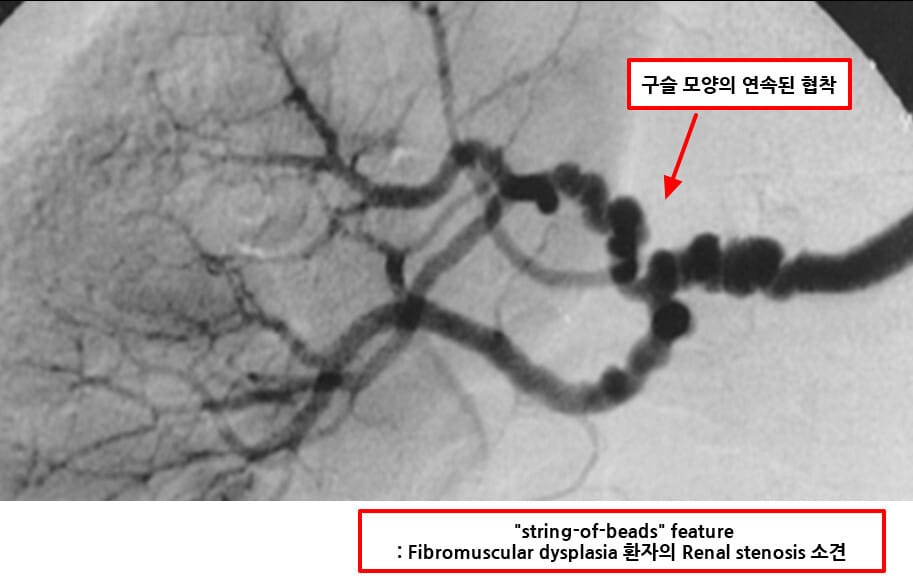

| 🔴 근육섬유형성이상(Fibromuscular dysplasia) |

| 젊은 여성에게 흔하며, 신동맥 중간~원위부에서 ‘string of beads’ 모양 협착이 나타납니다. |

| 🔴 구슬 모양이 연속된 형태의 협착 -근육섬유형성이상(FMD) |

| 근육섬유형성이상(FMD)에서 특징적으로 보이며, string of beads sign이라 부릅니다. |